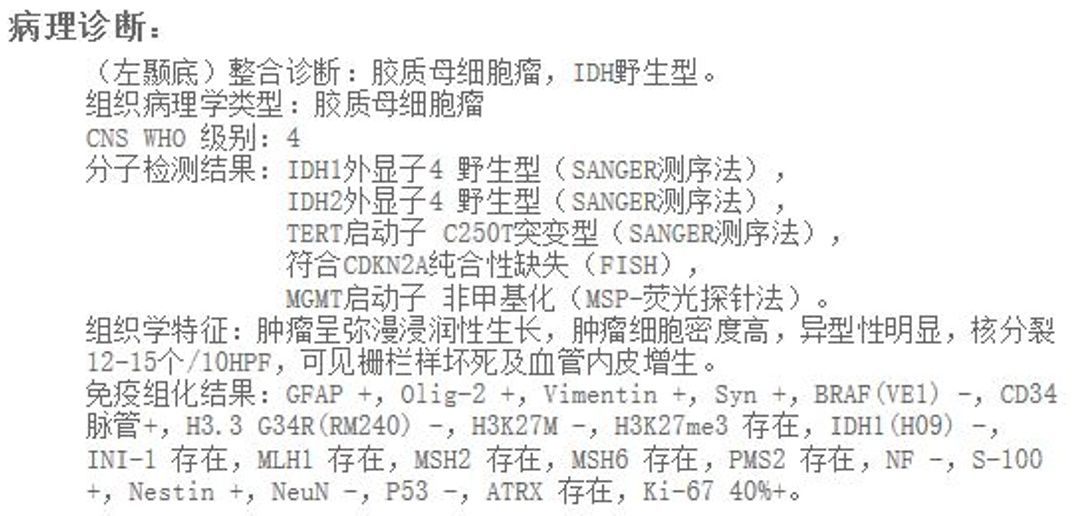

(一)左颞内侧巨大胶质母细胞瘤全切一例

术后病理提示胶质母细胞瘤,IDH野生型,MGMT非甲基化,预后相对较差。